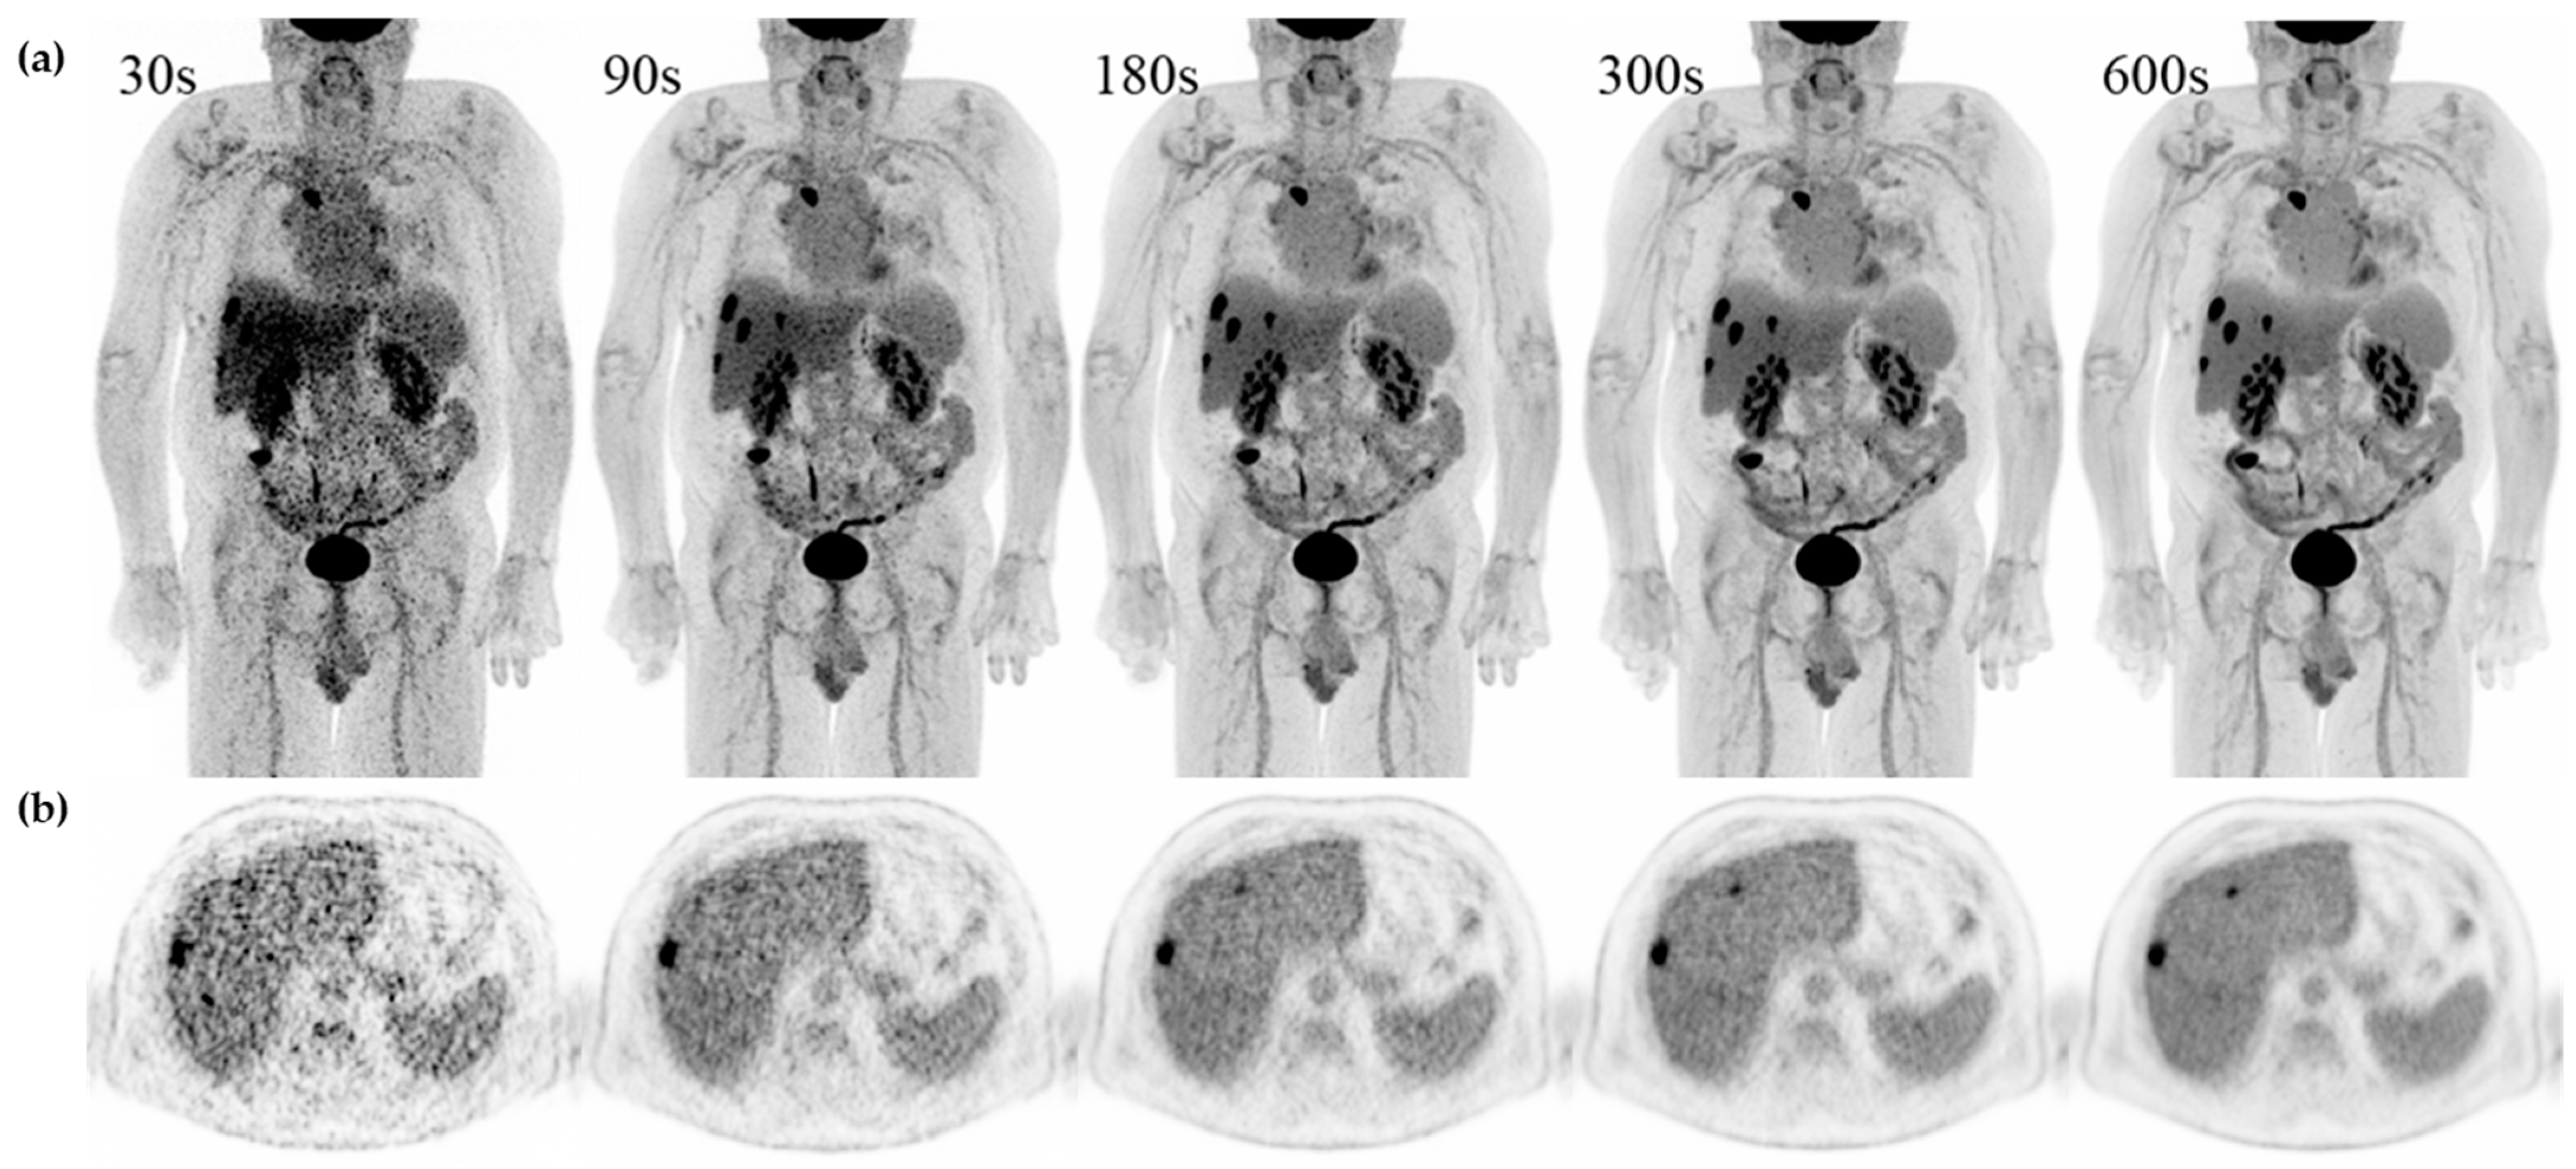

3.3. Image Quality

3.4. Lesion Detection